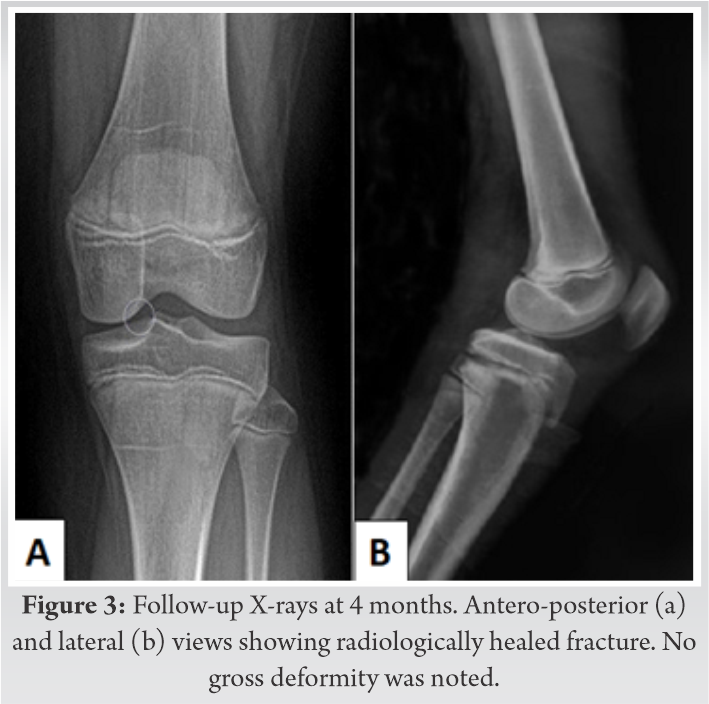

He was shifted to the operating room within 45 min of presentation. Under general anesthesia, in supine position, the fracture was reduced in a closed manner with traction and extension followed by flexion at the fracture site. Care was taken not to hyperextend or hyperflex the limb at any time during the maneuver. The reduction was held with two thick smooth K-wires in a crossed configuration (Fig. 2). The patient’s peripheral pulses had returned by the time the fixation was completed and hence the circulation was restored. Pin prick bleeding and capillary refill time returned back to normal. This was confirmed with a portable Doppler which showed biphasic flow in the peripheral arteries. Patient’s knee was immobilized in an above knee plaster cast. The post-operative period was uneventful except that the patient developed some blisters in the proximal leg on the 3rd postoperative day; however, there were no signs of any neurovascular compromise. The blisters were punctured, painted with Povidone-iodine and dressed in a dry manner. The skin healed well in a few days and the patient was discharged. The cast was removed at 3 weeks following which knee range of motion was started and the K-wires were removed at 6 weeks. Weight bearing was allowed at 3 months and gradually progressed as tolerable. Radiological healing was seen at 4 months (Fig. 3). At the last follow-up of 1 year, the patient had a good knee range of motion (ROM), no limb length discrepancy or deformity and was able to squat and sit cross legged without any difficulty.